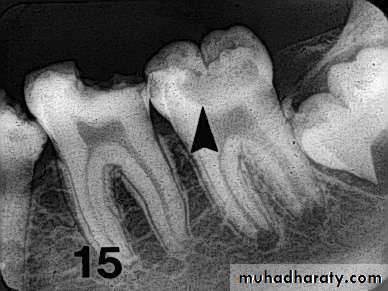

• Radiography

Carious lesions are detectable radiographically when there has been enough demineralization to allow it to be differentiate from normalThey are valuable in detecting proximal caries which may go undetected during clinical examination.

On average they have around 50% to 70% sensitivity in detecting carious lesions.

40% demineralization is required for definitive decision on caries